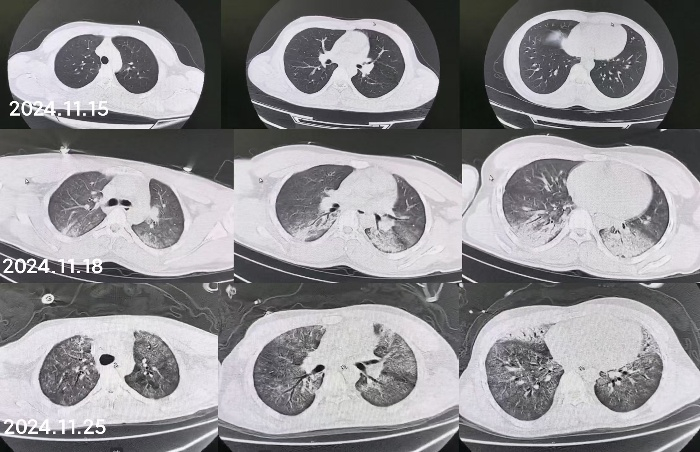

1 病例资料2024-11-15,某工地操作间有值班人员3人,分别为上铺(距地面1.8 m)A某,下铺(距地面0.4 m)B某、C某,事发当天为午休时间,设备出现故障,下午14时维修人员D某进入操作间维修,并将门窗打开,完成维修操作;事发后24 h内4名患者均出现不同程度的恶心、呕吐等消化道症状,起初考虑可能与食物中毒有关,前往当地医院就诊,完善血便常规、胸腹CT等相关检查未见明显异常,在医院给予吸氧补液静卧留观,留观期间4人先后出现不同程度的咽痛、咳嗽、胸闷、憋气等不适,吸氧不能缓解,再次行胸部CT检查示双肺弥漫性改变,间质改变可能,考虑为吸入有毒有害气体,后经采样检测操作间气体残留为全氟-4-甲基-2戊稀[Perfluoro(4-methylpent-2-ene),D1](D1纯度99.92%),导致急性呼吸窘迫综合症(acute respiratory distress syndrome, ARDS)。参照2002年职业性急性有机氟中毒诊断标准[1],A某诊断为急性中度有机氟气体中毒,B某、C某、D某诊断为急性重度有机氟气体中毒(PaO2/FiO2 < 100 mmHg,1 mmHg=0.098 kPa)。立即给予大剂量(120 mg)甲泼尼龙琥珀酸钠治疗,同时补充多种微量元素,加用甲钴胺、硫辛酸,钙剂解毒,后续加用特殊解毒剂乙酰胺治疗。治疗1周后,上铺的A某胸闷、憋气症状较前好转,影像未见明显进展,但患者仍遗留有间断气短症状;其余人员病情持续恶化,出现呼吸衰竭,转入重症医学科,给予气管插管接呼吸机辅助通气,维修人员D某上呼吸机后能基本维持,但不能脱机,继续观察患者病情变化;而下铺患者B某、C某症状不断加重,即使给予呼吸机治疗低氧状态仍未见明显改善,于2024-11-29转入本院进一步治疗。B某、C某入本院时查体:双肺叩诊呈清音,双肺呼吸音粗,可闻及干湿性啰音,具体指标见表 1,图 1、2为肺部影像进展情况。入院给予镇静镇痛、机械通气及抗感染、抗炎、抑酸等治疗,呼吸困难仍持续加重,存在难以纠正的低氧血症及高碳酸血症,表现为ARDS,有体外膜肺氧合(extracorporeal membrane oxygenation, ECMO)治疗指征,参考国内外相关救治经验[2-6],给予患者静脉-静脉ECMO(veno-venous extracorporeal membrane oxygenation, V-V ECMO)治疗,具体参数见表 2。

| 图 1 B某发病第1、3、10天胸部CT |

| 图 2 C某发病第1、3、10天胸部CT |

急性吸入性有机氟中毒常见于工业生产及废液处理中发生意外损伤,导致在短时间内吸入过量有机氟单体裂解气、残液气或热解气等所致的以呼吸系统损害为主的全身性损伤。急性肺损伤是其主要的病理生理学变化[9],其核心病理生理学基础是氧化应激及其介导的剧烈炎症级联反应[7],毒物吸入后,首先直接损伤肺泡上皮和毛细血管内皮细胞,导致血管通透性急剧增高[10],减少肺表面活性物质,造成肺与肺间质水肿、透明膜形成,这解释了本组患者早期均出现两肺弥漫性渗出的影像学表现。随后,活化的中性粒细胞和巨噬细胞释放大量氧自由基及蛋白酶,进一步破坏肺实质结构,形成肺泡隔增生致肺纤维化[11-12],并形成恶性循环。这即导致通气不足、弥散障碍、肺内分流增加和通气/血流比失衡,肺泡塌陷、细支气管闭塞、肺不张,最终导致ARDS,这一机制与本组病例中出现的呼吸困难及难以纠正的低氧血症和高碳酸血症(即ARDS)相符合。